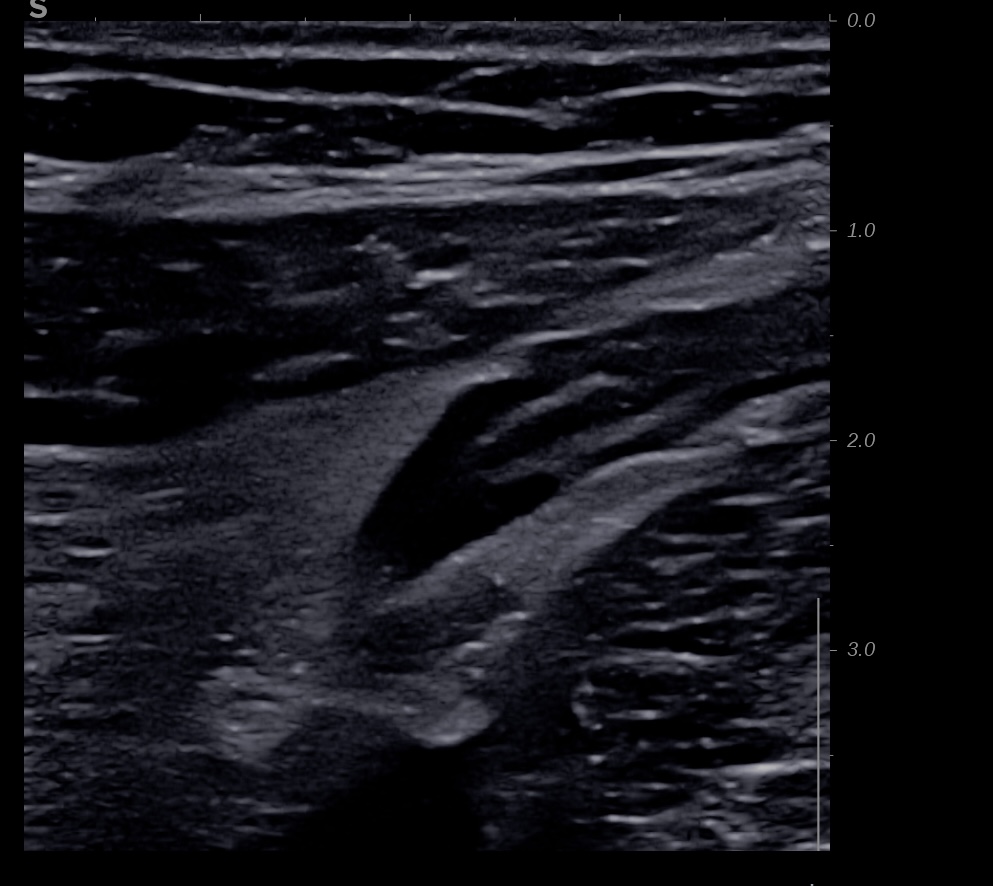

Echographie des cas numéro 2 puis 3

Epaississement entre 4.5 et 7 mm selon les segment, la structure en couche disparait totalement par endroit, à d’autre elle est partiellement conservée. Activité doppler intense de la paroi

Le Score de Milan (MUC) est à (1,4 x7+2) = 11,8

Là encore la paroi est très hypoéchogène, la structure en couches est par endroit totalement absente, ulcérations en surface, infiltration de la graisse, doppler intense, petites adénopathies périphériques.

Le rectum est bien vu avec la sonde basse fréquence la paroi atteint 10 mm à ce niveau.

Le score de Milan MUC est de (10 x1,4+2) = 16